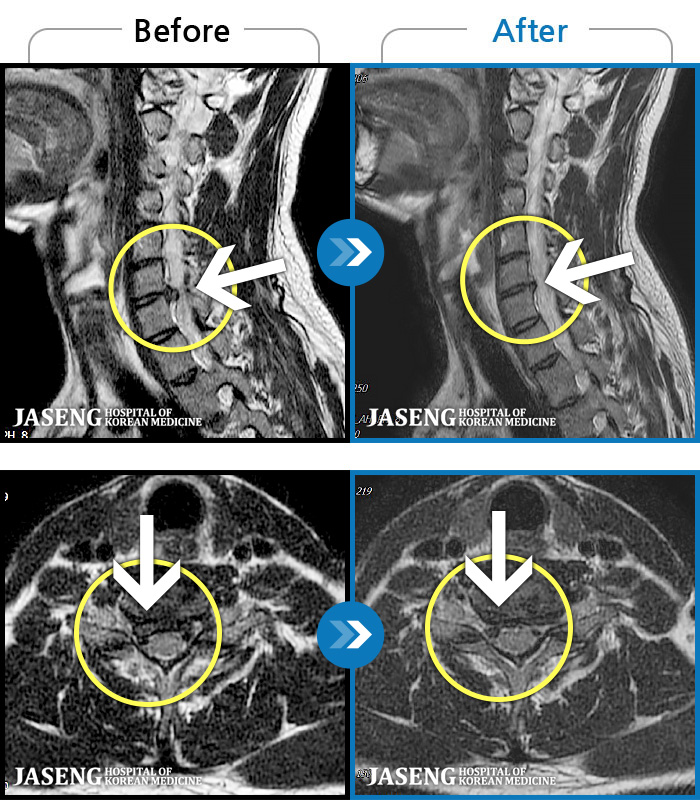

[ؿ] 24.10.10~25.04.23

ȯںп Ǹ ǿ ԿǾ, ο ġ ۿ Ƿ ġḦ Ͻñ ٶϴ.